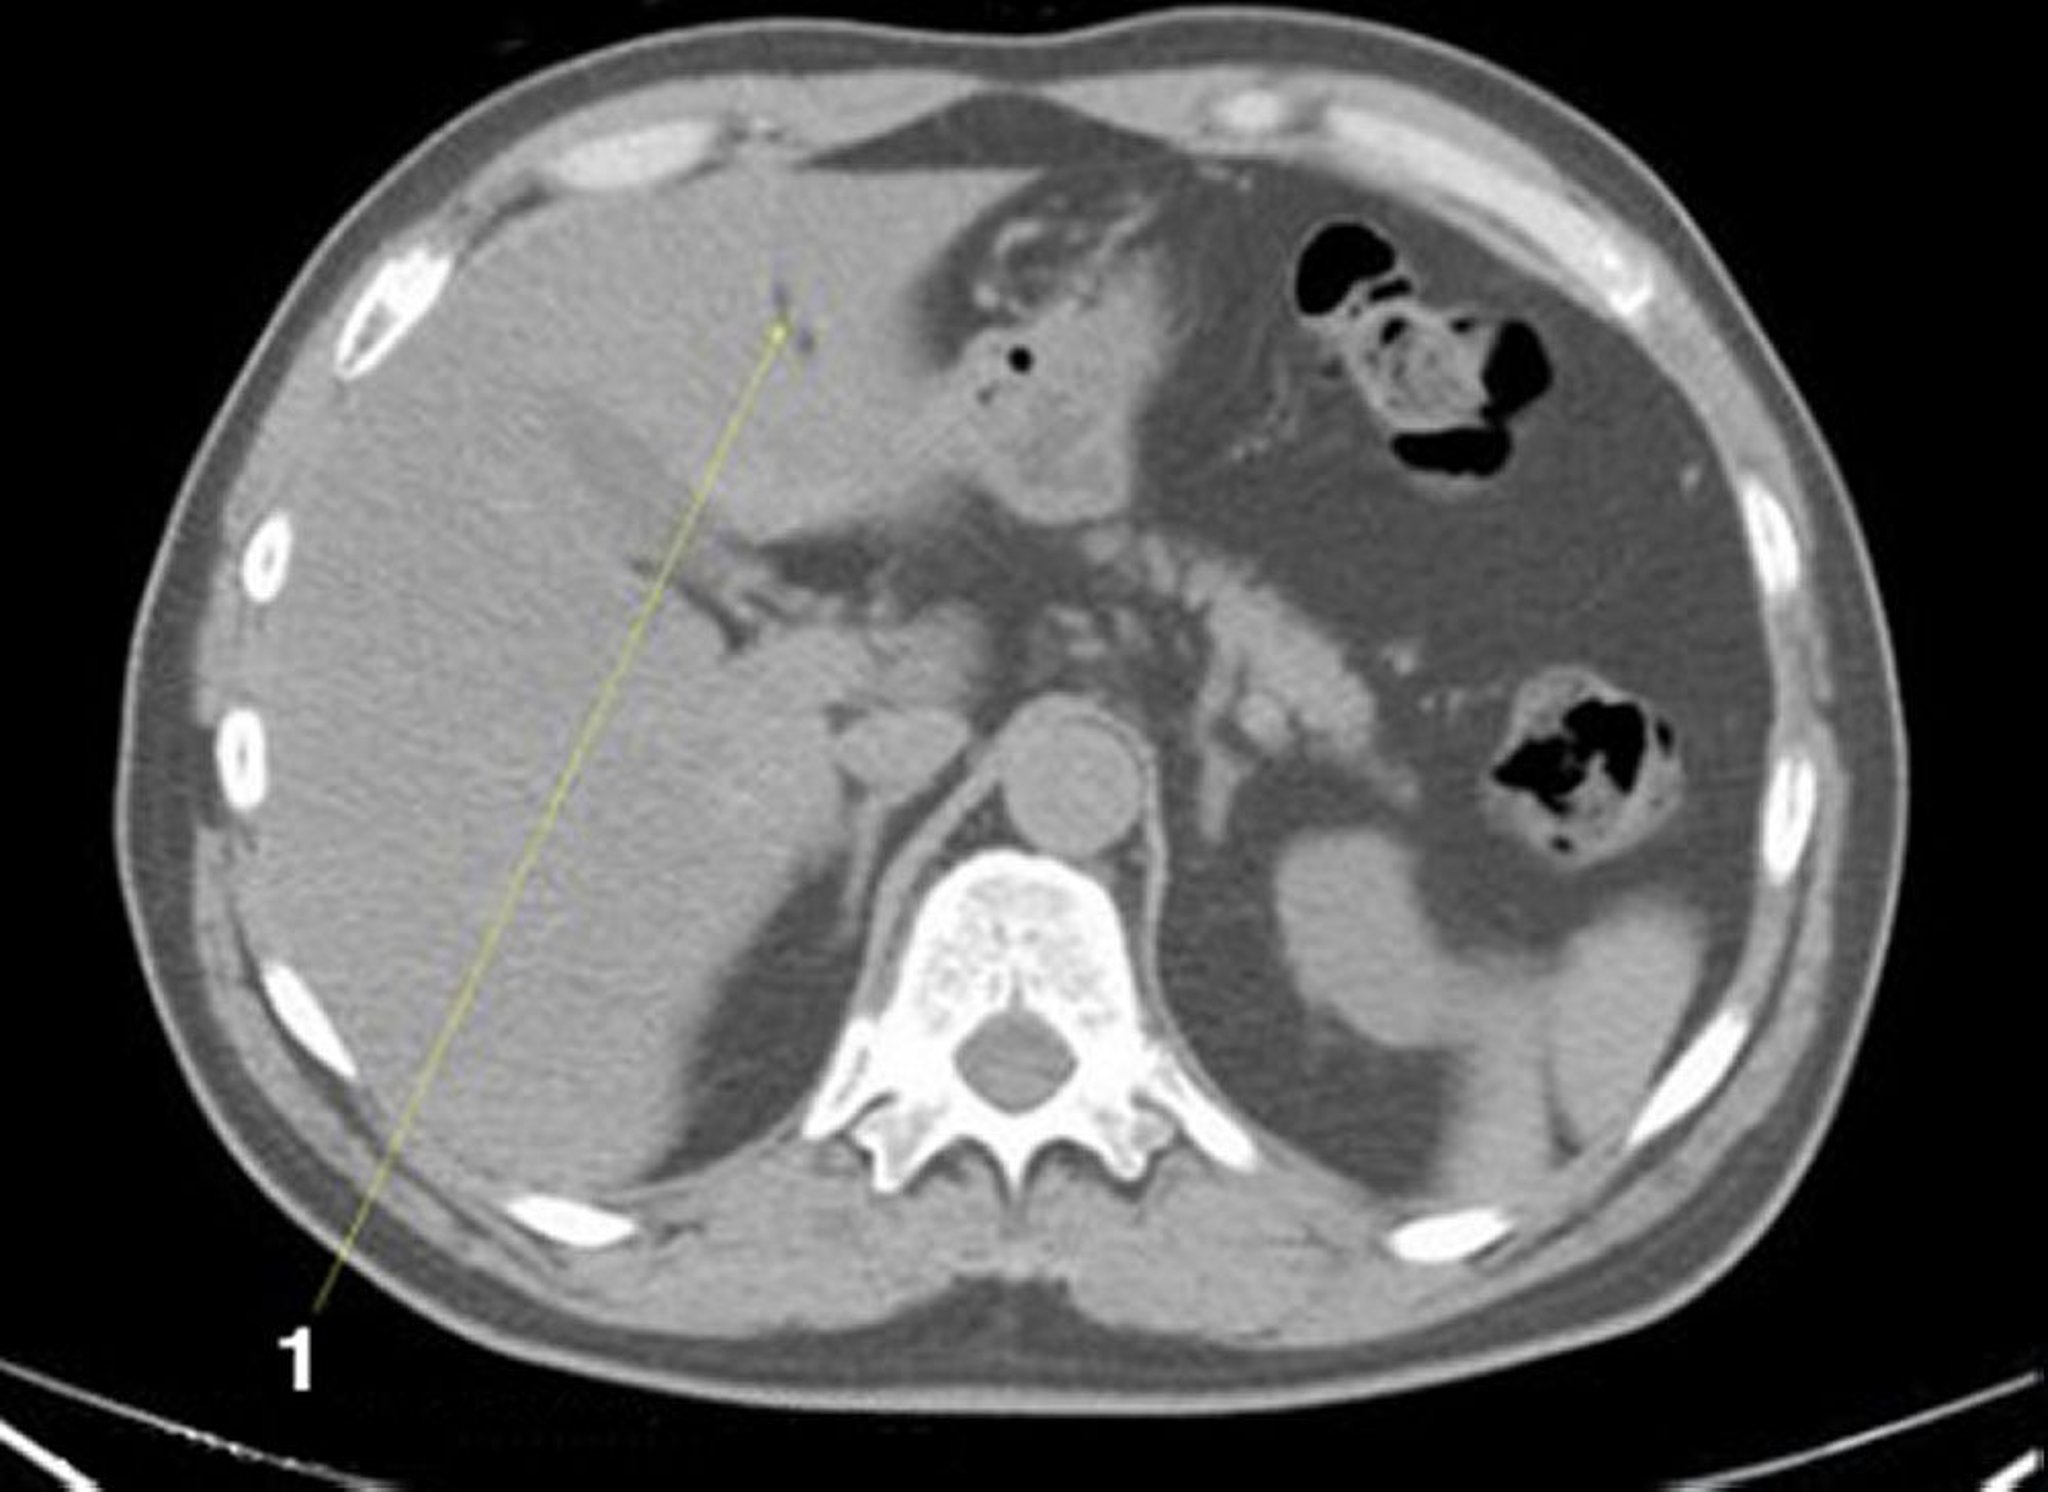

Tomografía computarizada sin contraste de abdomen y pelvis que muestra anatomía normal (corte 5)

1 = fisura del ligamento amarillo.